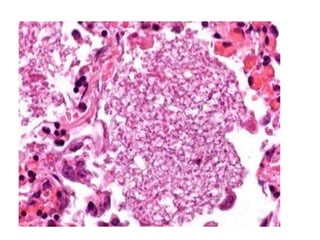

• #17 10 x

• #18 10 x Granulomatous inflammation, large thick-walled spherules contain variable sized daughter cysts ? Pyogenic reaction occurs with release of endospores from rupture of spherules ? Variable fibrocaseous granulomata, military disease, pyogenic inflammation ? Immature nonendosporulating spherules can resemble nonbudding forms of Blastomyces dermatitidis (Can Respir J 2008;15:377)

• #19 GMS Ten x

• #20 Barrel shaped structure arthroconidia-are a type of fungal spore typically produced by segmentation of pre-existing fungal hyphae

• #21 This well-formed granuloma has a large Langhans giant cell in the center. Two small spherules of Coccidioides immitis are seen within the cytoplasm of the giant cell.

• #22 Histoplasma- thin based pear shaped yeast cells Coccidomycosis- thick walled non- budding spherule 20 60 micron in diAMETER Blasto- 5- 15 micron yeast cells that divide by broad based budding . It has thick double contoured cell wall and a visible nucleus